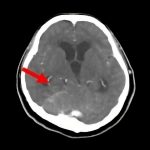

断層撮影